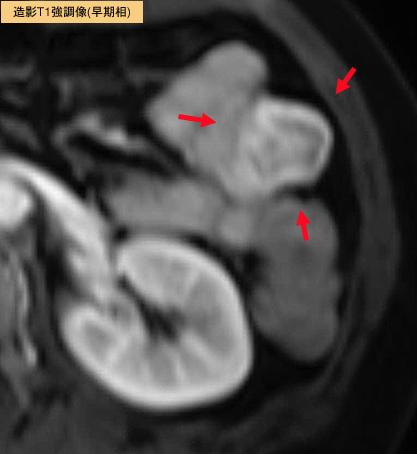

A case of a gastrointestinal stromal tumor (GIST) in the jejunum.

Malignant non-epithelilal tumors/Leiomyosarcoma (including GIST)

Small intestine/Ileum

MRI

30 - 34

serosa (adventitia)